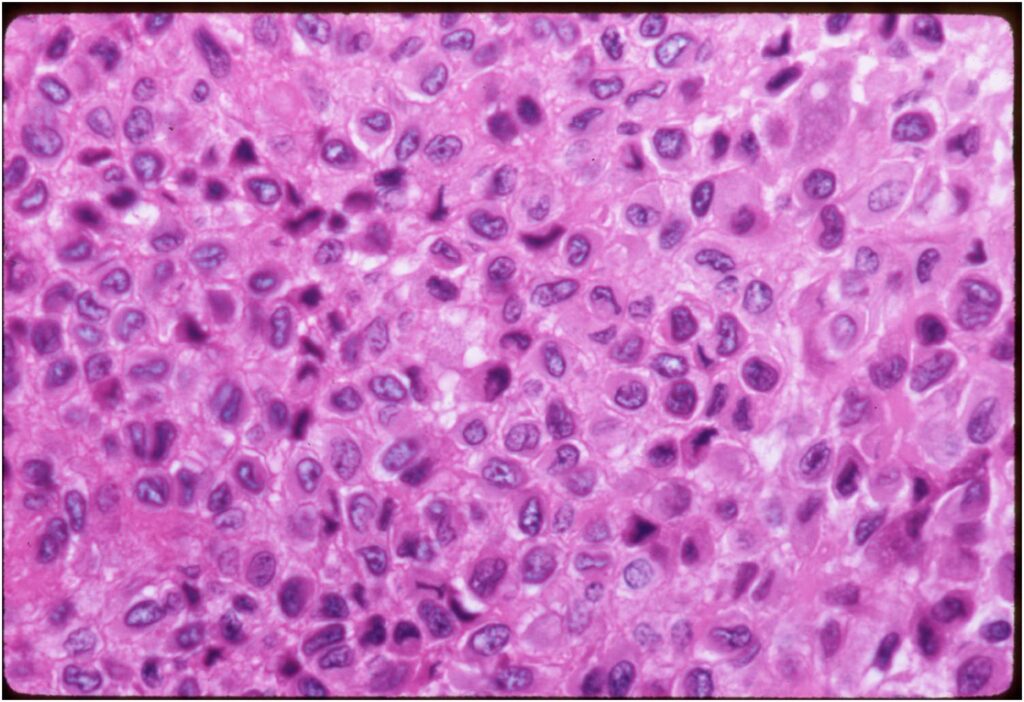

Microscopic Pathology

- Variable appearance depending on percentage of cells, necrosis, cartilage matrix formation and ABC change

- Chondroid matrix in up to 15% of tumor

- ABC component 5-15% of tumors

- The tumor is composed of chondroblasts that have a distinct, thick cell membrane. The thick cell membrane gives it a “Chicken Wire Fence Appearance,” especially when the cell membranes are calcified